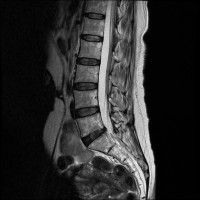

목,허리 디스크 엠알 판독.....

경추 요추 디스크 둘다 있는 상태고 경추몇번에서 몇번사이 요추몇번에서 몇번사이인지 알려주세요

허리

• 3번 째 사진